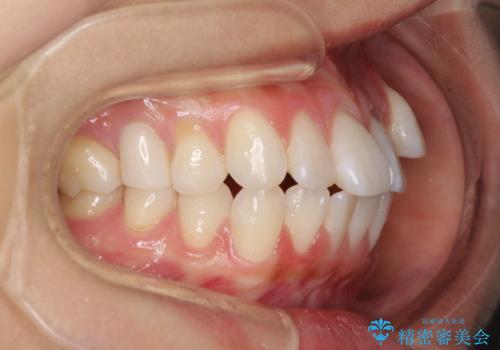

- 八重歯と口元の突出感を気にして来院された患者様です。

歯列が前方に突出しており、上下の正中がズレていたため、左側は上下第一小臼歯を、右側は上下第二小臼歯を抜去し、ワイヤー装置による矯正治療を行うこととしました。

当初はインビザラインによる矯正治療をご希望でしたが、正中を合わせたいことや、口元の突出感を改善したいことから、ワイヤー矯正を強く推奨しました。

治療期間は2年に満たず、スッキリとした口元に仕上がりました。